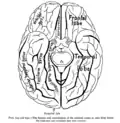

Базальная поверхность мозга, прямая извилина отмечена красным

- Нижняя проекция мозга